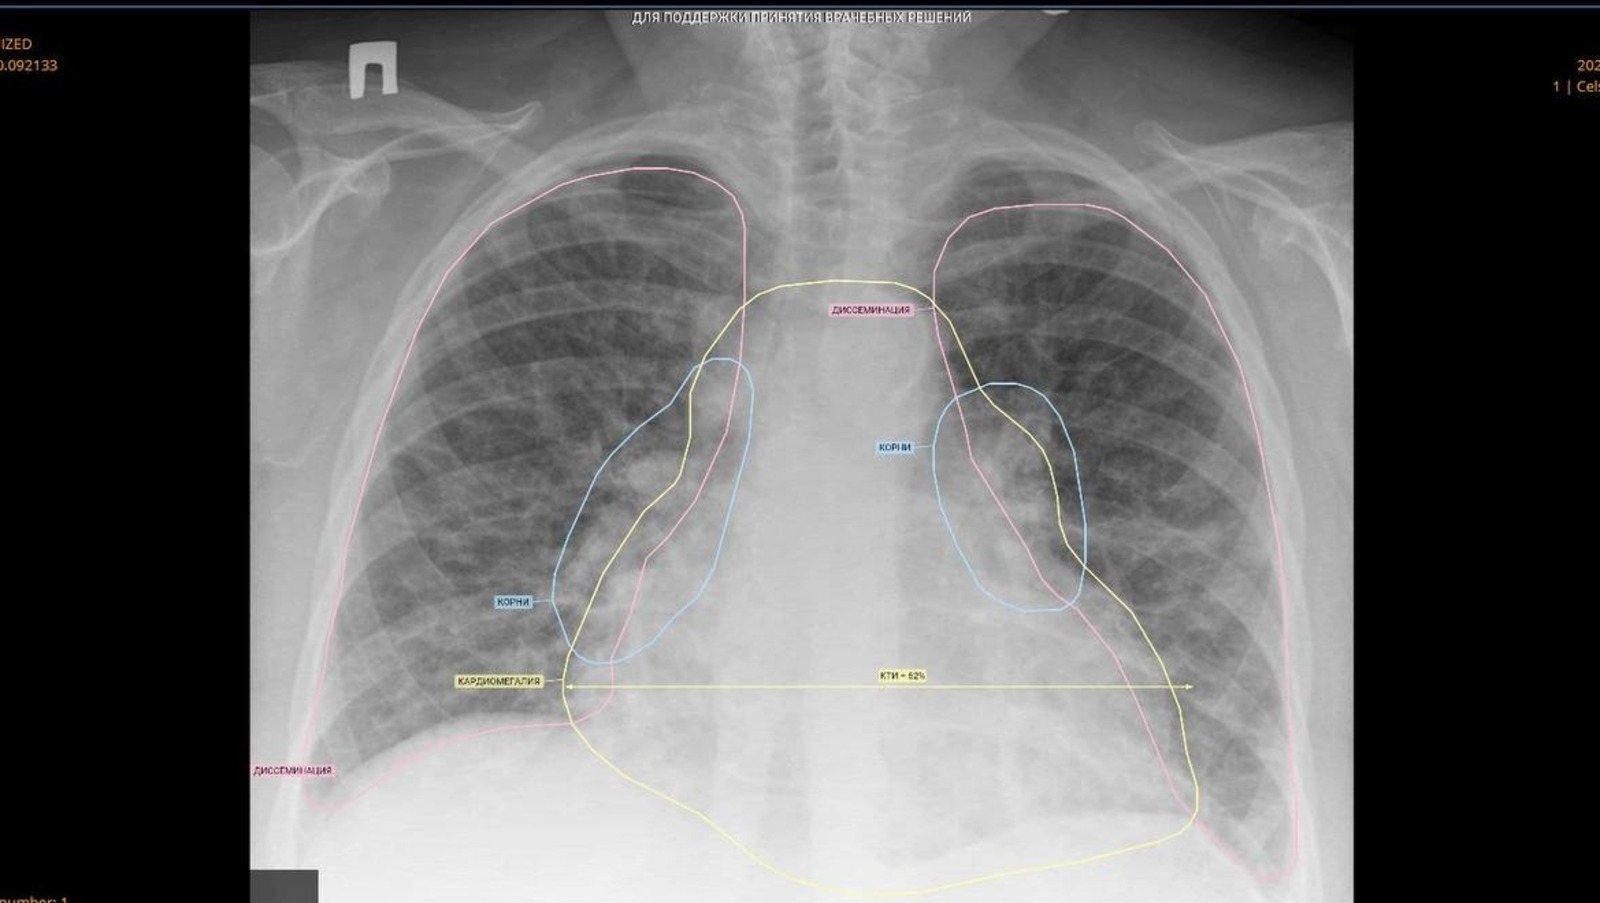

В Башкирии искусственный интеллект помогает медикам диагностировать заболевания. Всего за два месяца работы с платформой «МосМедИИ» искусственный интеллект помог проанализировать 1,7 тысячи медицинских изображений, рассказал в своем телеграм-канале министр здравоохранения республики Айрат Рахматуллин.

«Наша республика стала одной из первых субъектов РФ, которые подключились к платформе, объединяющей 17 сервисов для анализа КТ, рентгенографии, маммографии и флюорографии. Система демонстрирует впечатляющую скорость: на обработку 100 снимков искусственному интеллекту требуется всего 3 минуты, в то время как врачу — около часа», — отметил Айрат Рахматуллин.

Министр добавил, что до конца года проект планируется распространить на все медицинские организации республики. А также указал на то, что цифровые технологии выступают только помощником врача, окончательное решение всегда остается за медицинским специалистом.